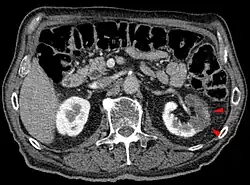

Der Verschluss einer Arterie, deren Endstromgebiet auch von einer Kollateralen versorgt wird, führt zum hämorrhagischen Infarkt (Beispiel: Lungeninfarkt).

Obwohl der betroffene Bezirk mit Blut aus mindestens einer Kollaterale versorgt wird, kommt es aufgrund des zu geringen Blutflusses zur Sauerstoffunterversorgung. Es folgt eine Nekrose mit Untergang des Gefäßendothels. Die daraus resultierende Einblutung ins Gewebe führt zu der typischen Rotfärbung („roter Infarkt“).

- Lungeninfarkt, meistens durch eine Lungenembolie bedingt